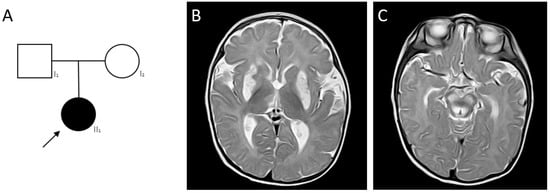

2.4. Clinical Cases